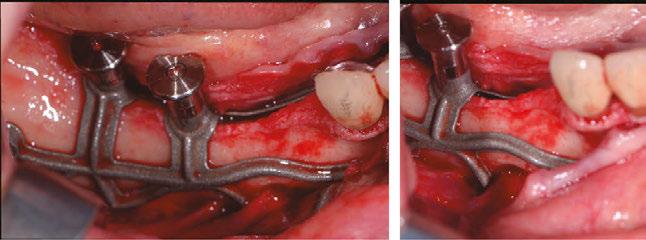

2. Surgical protocol

The procedure is performed under local anesthetic and lasts between 1 and 1-1/2 hours per side.

The first step is to raise a flap wide enough to allow adequate access to the surgical site. The crestal incision is made so as to evenly distribute the attached gingiva on either side of the future abutments. It extends to the anterior teeth via an intrasulcular incision and ends along the anterior edge of the ascending ramus.

The aim is to create full-thickness flaps to expose the chin foramen and protect the inferior alveolar pedicle (nerve) on the vestibular side. The detachment should then continue beyond the external oblique line to the basal margin of the mandible, then to the insertion of the buccinator muscle without detaching it.

On the lingual side, it is also important to push back the sublingual compartment by lifting, still in full thickness, to the medial oblique line posteriorly and apically up to the anterior digastric fossa, avoiding effraction of the mylohyoid muscle and mental spines (Figures 6 and 7).12

Some clinicians may choose to use a technique for one-piece subperiosteal implants. However, the author notes that one-piece bilateral subperiosteal implants are more difficult to insert, making surgery more complex. The surgery

Figure 8 (left): The Panthera SUB implant is gripped to facilitate insertion without damaging it. Figure 9 (right): Positioning the implant and checking its fit (occlusal view)

Figure 6 (left): Preoperative situation, panoramic radiograph and intraoral photo. Figure 7 (right): Incisions and flap detachment